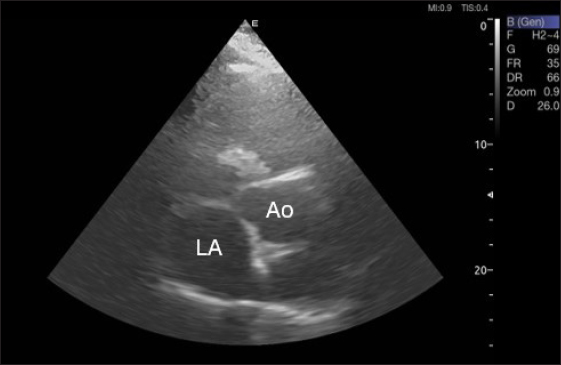

Right parasternal ultrasonography

By positioning the probe perpendicularly in the fourth intercostal space or longitudinally in the fifth space with a little clockwise rotation, the interventricular septum, ventricles, and atria could be observed in the caudal long-axis four-chamber view (Fig. 1). From this vantage point, all camels could be seen to have a left ventricle, mitral valve, interventricular septum, right ventricle, and tricuspid valve. Figure 2 shows that in the short-axis image of the cardiac ventricles obtained with a little clockwise rotation at the 4th ICS, only the right ventricle, interventricular septum, and left ventricle were visible. Here, the dimensions of all camel heart were measured in M mode. The right parasternal two-dimensional short-axis pictures of the heart’s base in the first frame were used to determine the LA/Ao ratio, by applying 2D and M mode (Figs. 3 and 4). Despite some difficulties, we successfully acquired a pulmonary image by attempting to acquire the right ventricular outflow tract for the right short axis at the level of the great vessels.

Fig. 3. Right parasternal short-axis view of 16 she-camel at great vessel level showing Ao=aorta and LA=left atrium.